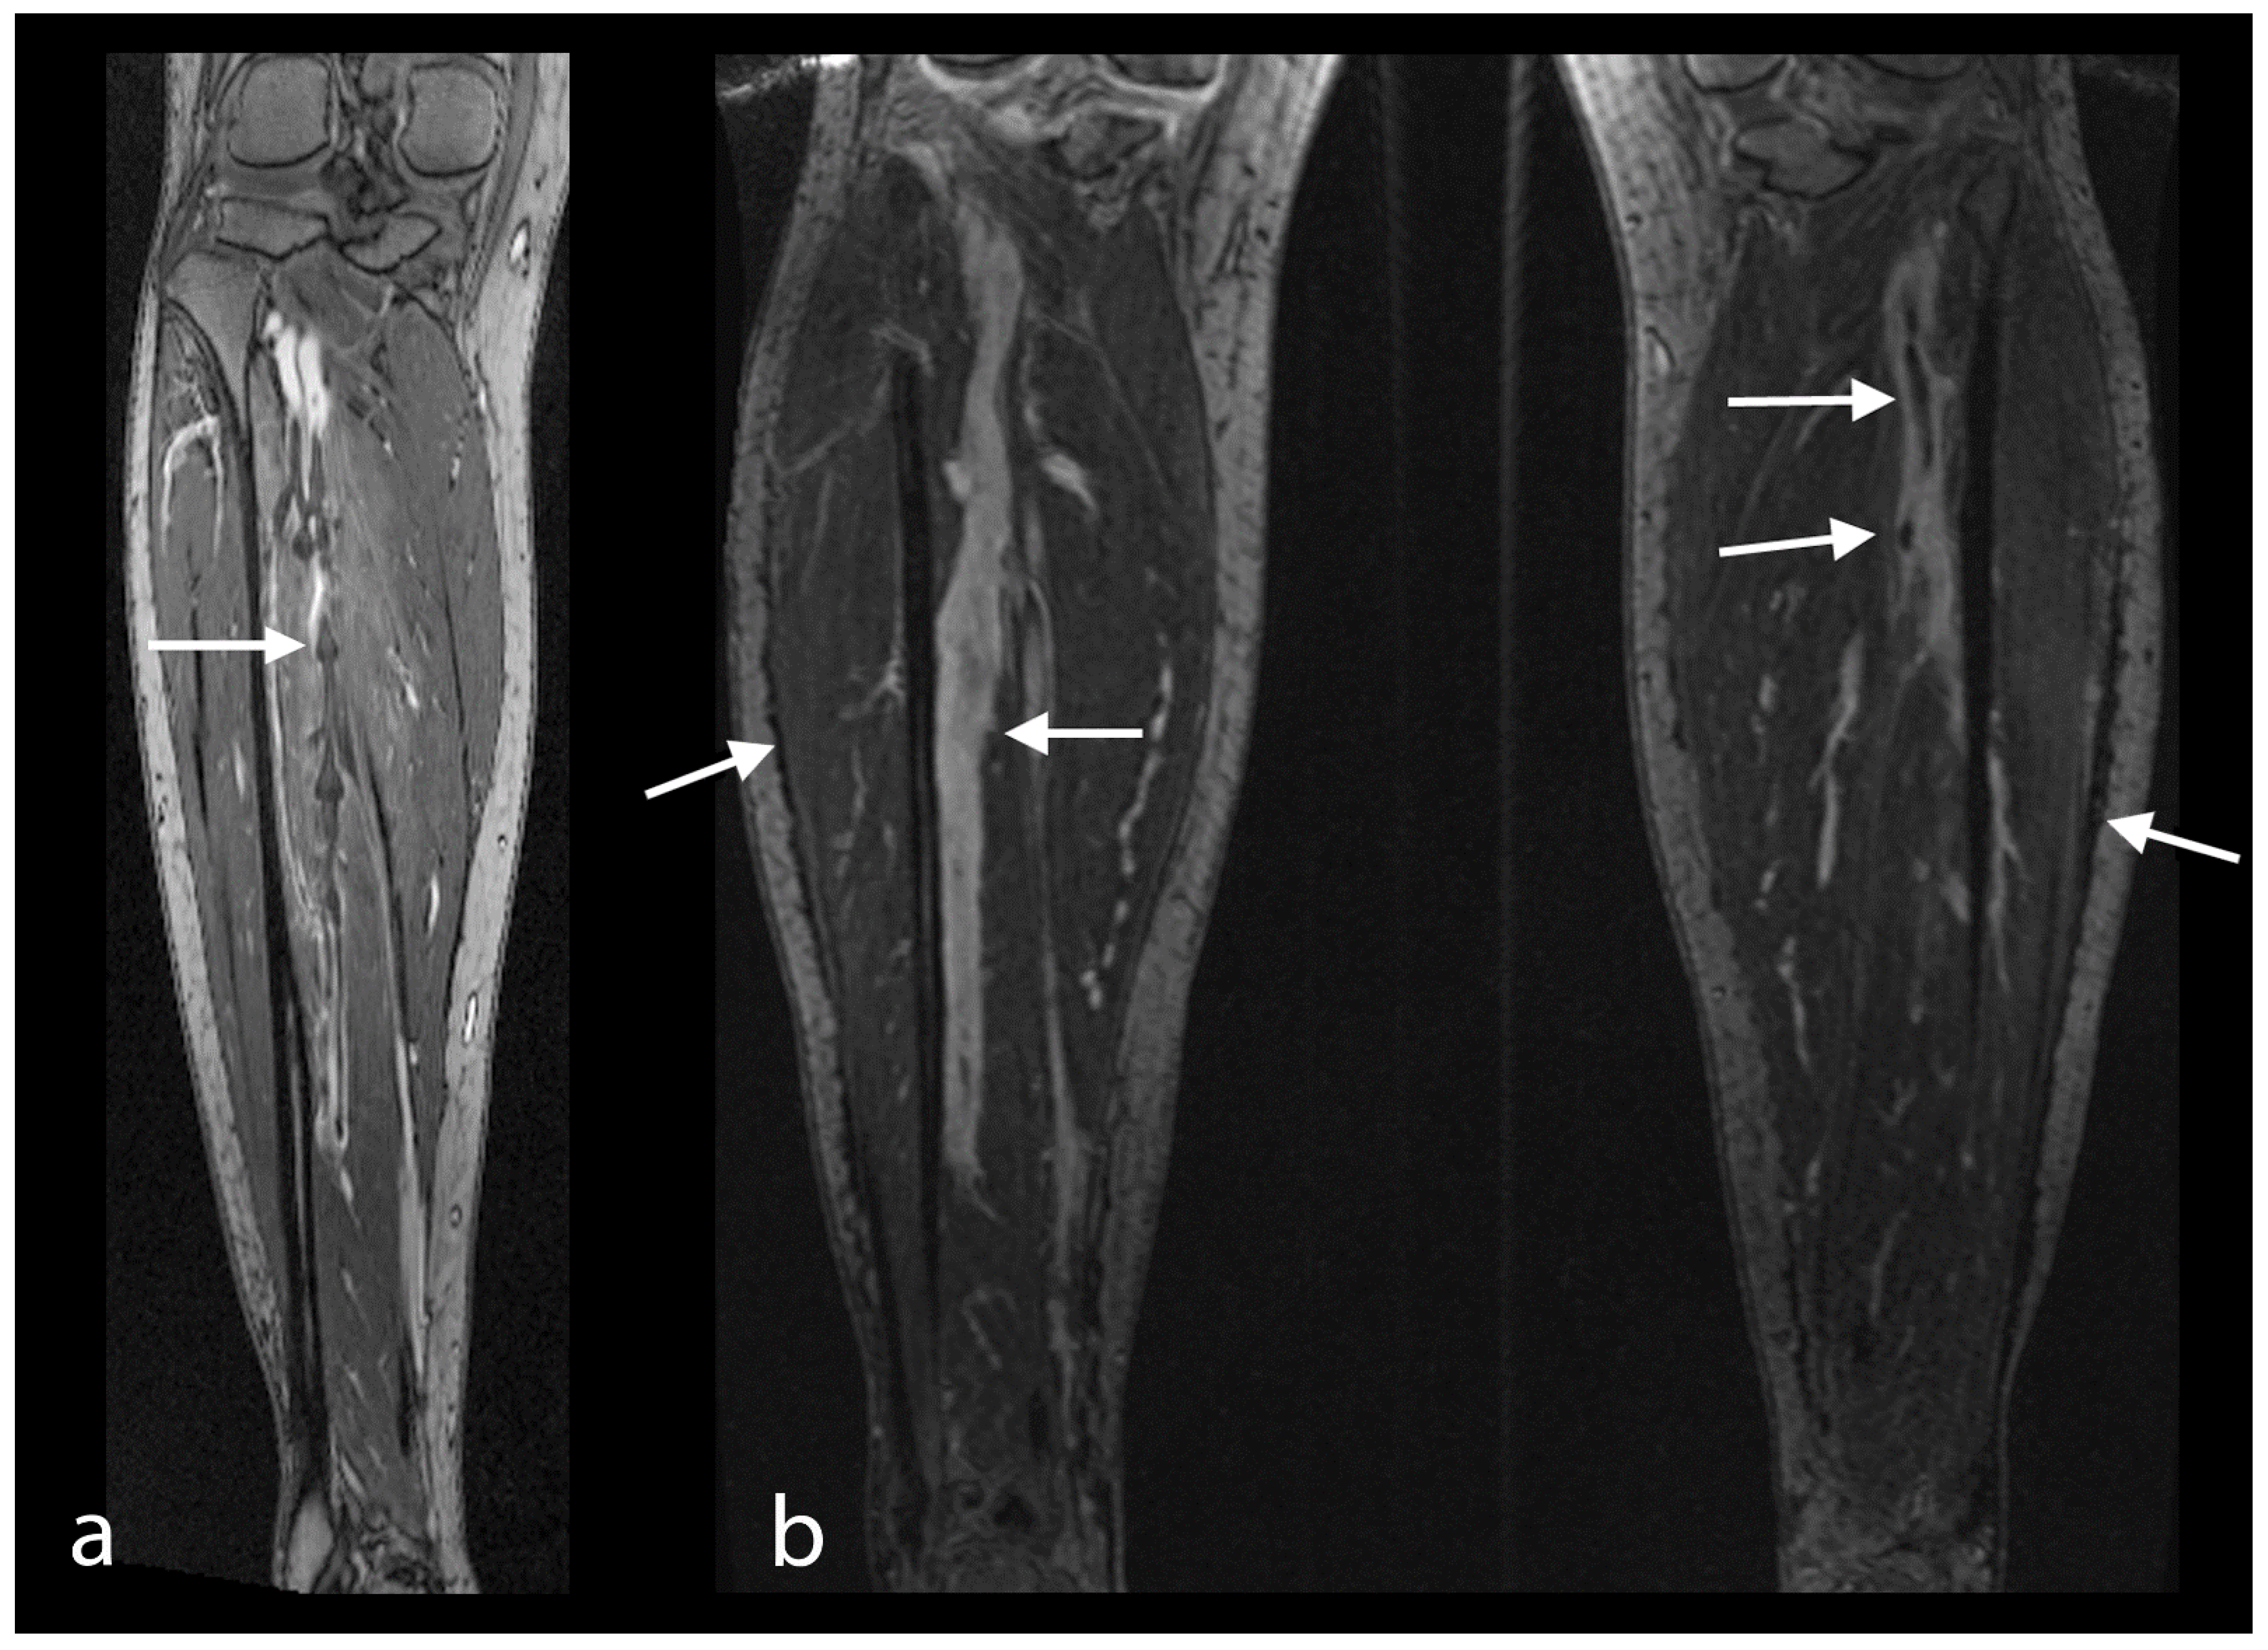

- Enden, T.; Storås, T.H.; Negård, A.; Haig, Y.; Sandvik, L.; Gjesdal, K.I.; Sandset, P.M.; Kløw, N.E. Visualization of deep veins and detection of deep vein thrombosis (DVT) with balancec turbo field echo (b-TFE) and contrast-enhanced T1 fast field echo (CE-FFE) using a blood pool agent (BPA). J. Magn. Reson. Imaging 2010, 31, 416–424. [Google Scholar] [CrossRef]

- Aschauer, M.; Deutschmann, H.A.; Stollberger, R.; Hausegger, K.A.; Obernosterer, A.; Schöllnast, H.; Ebner, F. Value of a blood pool contrast agent in MR venography of the lower extremities and pelvis: Preliminary results in 12 patients. Magn. Reson. Med. 2003, 50, 993–1002. [Google Scholar] [CrossRef]